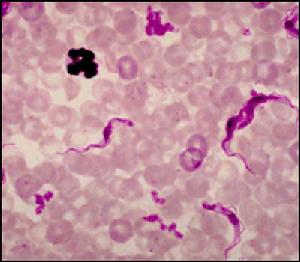

布氏錐蟲的血液塗片

布氏錐蟲的血液塗片自然感染病例的潛伏期約為10天。馬屬動物發病時體溫迅速升高至40~41℃ ,患畜精神不振,食慾下降,脈搏快而弱;結膜潮紅,結膜有時雜有小出血,眼中流淚;鼻孔中流出漿性鼻液;四肢、腹下、外陰部周圍、喉部和眼瞼發生界限明顯的水腫。

發熱維持2~3天,有時1周,然後體溫迅速下降至正常或甚至正常以下,臨診症狀減輕或消失。經過一定時間後又重新發熱。如此反覆發作後,患畜日益消瘦,逐漸發生在高度貧血,白紅蛋白量可降至正常值的25%,紅細胞數可降至250萬,白細胞中度增多。黏膜初期蒼白,後期黃疸。最後患畜極度瘦弱,運動失調後搖擺不定,最終因極度衰竭而死亡。在頭幾次發熱時,血液中有大量布氏錐蟲,後來減少。只有當重新發熱時才又大量出現。

(2)病原學檢查。取病畜1滴血液加等量生理鹽水直接在顯微鏡下檢查。也可取病畜血液、淋巴液、腦脊液後骨髓穿刺液作塗片鏡檢。患畜在發熱期間常能在外周血液中查到蟲體。